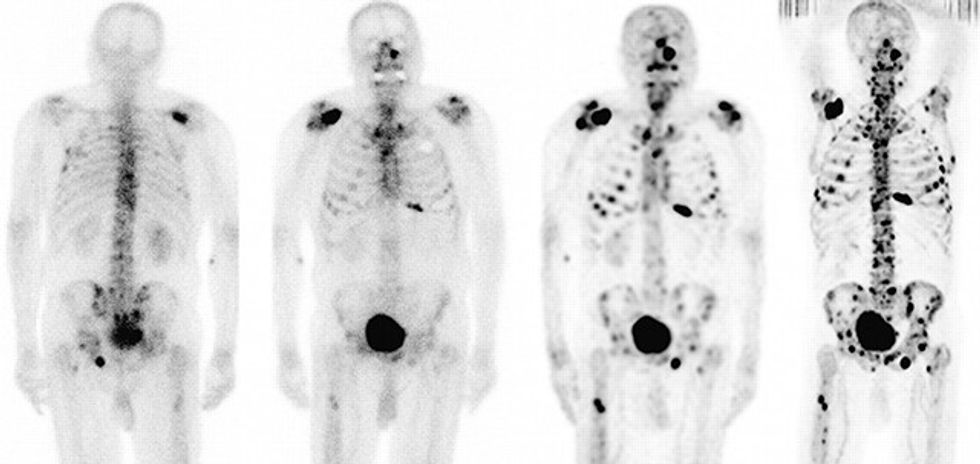

Për shkak të spektrit të ndryshëm të simptomave, kanceri i eshtrave është sëmundje e rrezikshme e cila shpesh diagnostikohet gabimisht.

Kanceri i eshtrave është tip shumë i rrallë i kancerit i cili kryesisht zhvillohet ngjashëm me artritin dhe bëhet më i keq gjatë natës.

Reagimi i shpejtë me incizimin e eshtrave në rëntgen mund të shtohen shanset e të sëmurëve për mbijetesën e nga kjo sëmundjeje e rrezikshme.